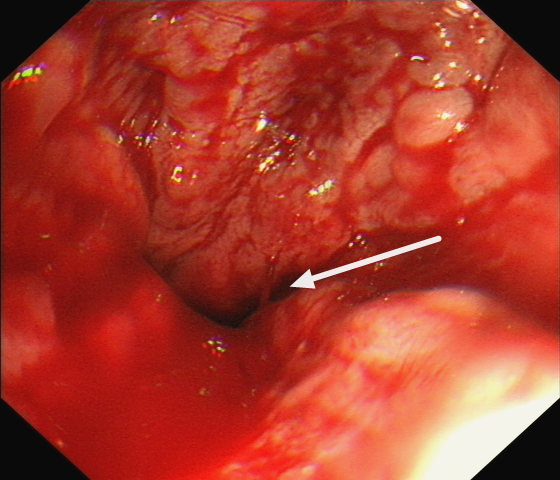

家住桃源的周女士,几天前发现大便变黑,次日又出现呕血,总量约1200ml。家人马上带她到湘雅常德医院消化内科就诊,并以“上消化出血”收治住院。    入院后,伍丽医师仔细询问病...